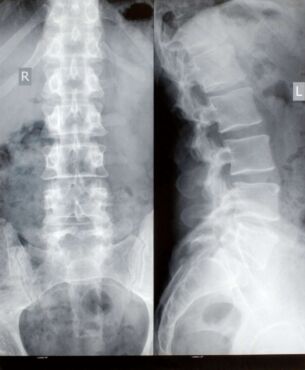

Röntgenové lúče prechádzajú telom, sú absorbované v rôznych množstvách tkanivami v závislosti od ich hustoty (denzity). Najlepšie bývajú zobrazené kostné štruktúry.

Hustejšie materiály, ako kosti či kovy, sú zobrazené na röntgenových snímkach biele. Na druhej strane, vzduch, napríklad v pľúcach, zobrazuje sa čiernou farbou. Tuk a svaly sa zobrazujú ako odtiene šedej.

- Kosti a zuby – k odhaleniu zlomenín (fraktúr) a infekcií, zápalov kĺbov, zubného kazu (dutín v zuboch), osteoporózy a rakoviny kosti